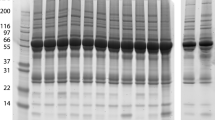

To identify host proteins affected by scrub typhus infection, serum samples were prepared from normal subjects (controls), naive patients (before antibiotic treatment) and treated patients (after antibiotic treatment), then analysed by GeLC-MS/MS. From the proteomic analysis, 174, 155 and 143 human proteins were identified in the serum of normal subjects, naive scrub typhus patients and treated patients, respectively (Fig. 1 and Additional file 2: Table S1). Following infection with O. tsutsugamushi, expression of 70 proteins was significantly up-regulated, and expression of 94 proteins was down-regulated, compared with normal subjects (Table 2). After antibiotic treatment, 26 proteins were up-regulated and 36 proteins were down-regulated in treated patients relative to naive patients (Table 2). These proteins could be useful for investigating the pathophysiology of scrub typhus at the molecular level, and for discovering diagnostic biomarkers of O. tsutsugamushi infection. The quantitative results also revealed that the number of proteins expressed at similar levels in normal subjects and naive patients was 60 (26.8%), while the number between naive patients and treated patients was 113 (64.6%), indicating that protein expression was more similar between treated patients and naive patients than between treated patients and normal subjects (Table 2). This may suggest that treated patients are in the process of recovery, but not fully recovered.